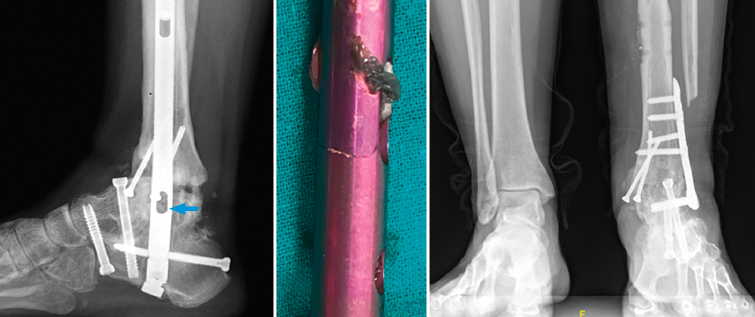

La paciente presentó un postoperatorio dentro de la normalidad pero, a los 2 años de evolución, empezó a presentar molestias en el tobillo. Se realizaron Rx y TAC donde se objetivó consolidación de la articulación subtalar pero pseudoartrosis a nivel tibiotalar, con rotura incompleta del clavo y del cerrojo del calcáneo colocado en sentido posteroanterior.

Figura 6. Imagen radiográfica y clínica en la que se aprecia la rotura parcial del clavo. Rescate con placa tibiotalar en proyección radiográfica en carga.

En este caso, la extracción fue sencilla: una vez retirados los tornillos de bloqueo, se realizó, con el sistema extractor del clavo, la extracción del mismo sin dificultad, ya que se trataba de una rotura incompleta. Realizamos un nuevo legrado de las superficies óseas, perforación de las mismas, nuevo aporte de injerto de cresta ilíaca y fijación con placa de artrodesis tibiotalar (Palex Medical), ya que la articulación subtalar estaba consolidada (Figura 6).